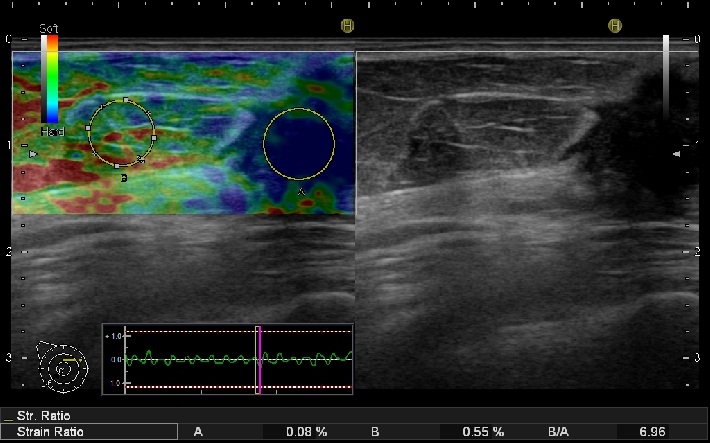

硬さをみるエラストグラフィー

血流をみるカラードプラ